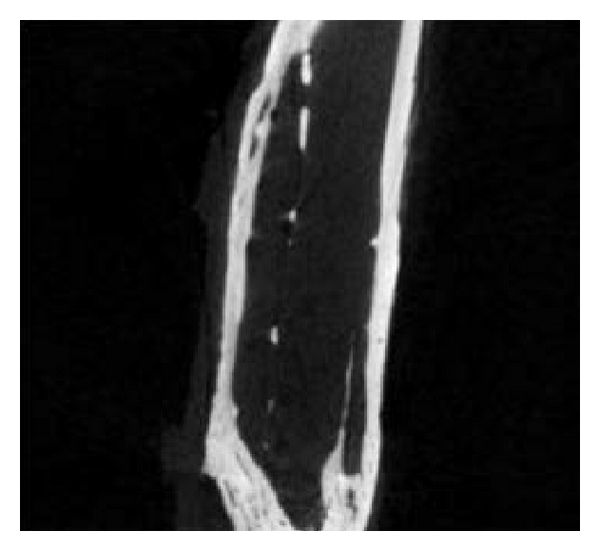

3.4. Micro-CT Examination

Micro-CT examination of 5 rabbits (2 from group A, 2 from group B, and 1 from group C) was conducted 3 months after surgery. The shapes of the rabbit bones at 3 months were shown in Figure 4. The bone defect in group A was not completely repaired, which in group B was completely repaired, while group C showed typical bone nonunion. The number of trabeculae per mm in groups A, B, and C was 0.40, 0.17, and 0.34, respectively. The bone mineral density in groups A, B, and C was 1.25434 mg/cc, 1.32521 mg/cc, and 1.3349 mg/cc, respectively, and the high bone density in group C resulted from osteosclerosis. The mass losses of PLLA and PLLA/PCL were 63.575% and 67.195%, respectively. These two scaffolds have fast initial degradation rate and then slowed down and cannot completely degrade 3 months after implantation.

(a)

(b)

(c)